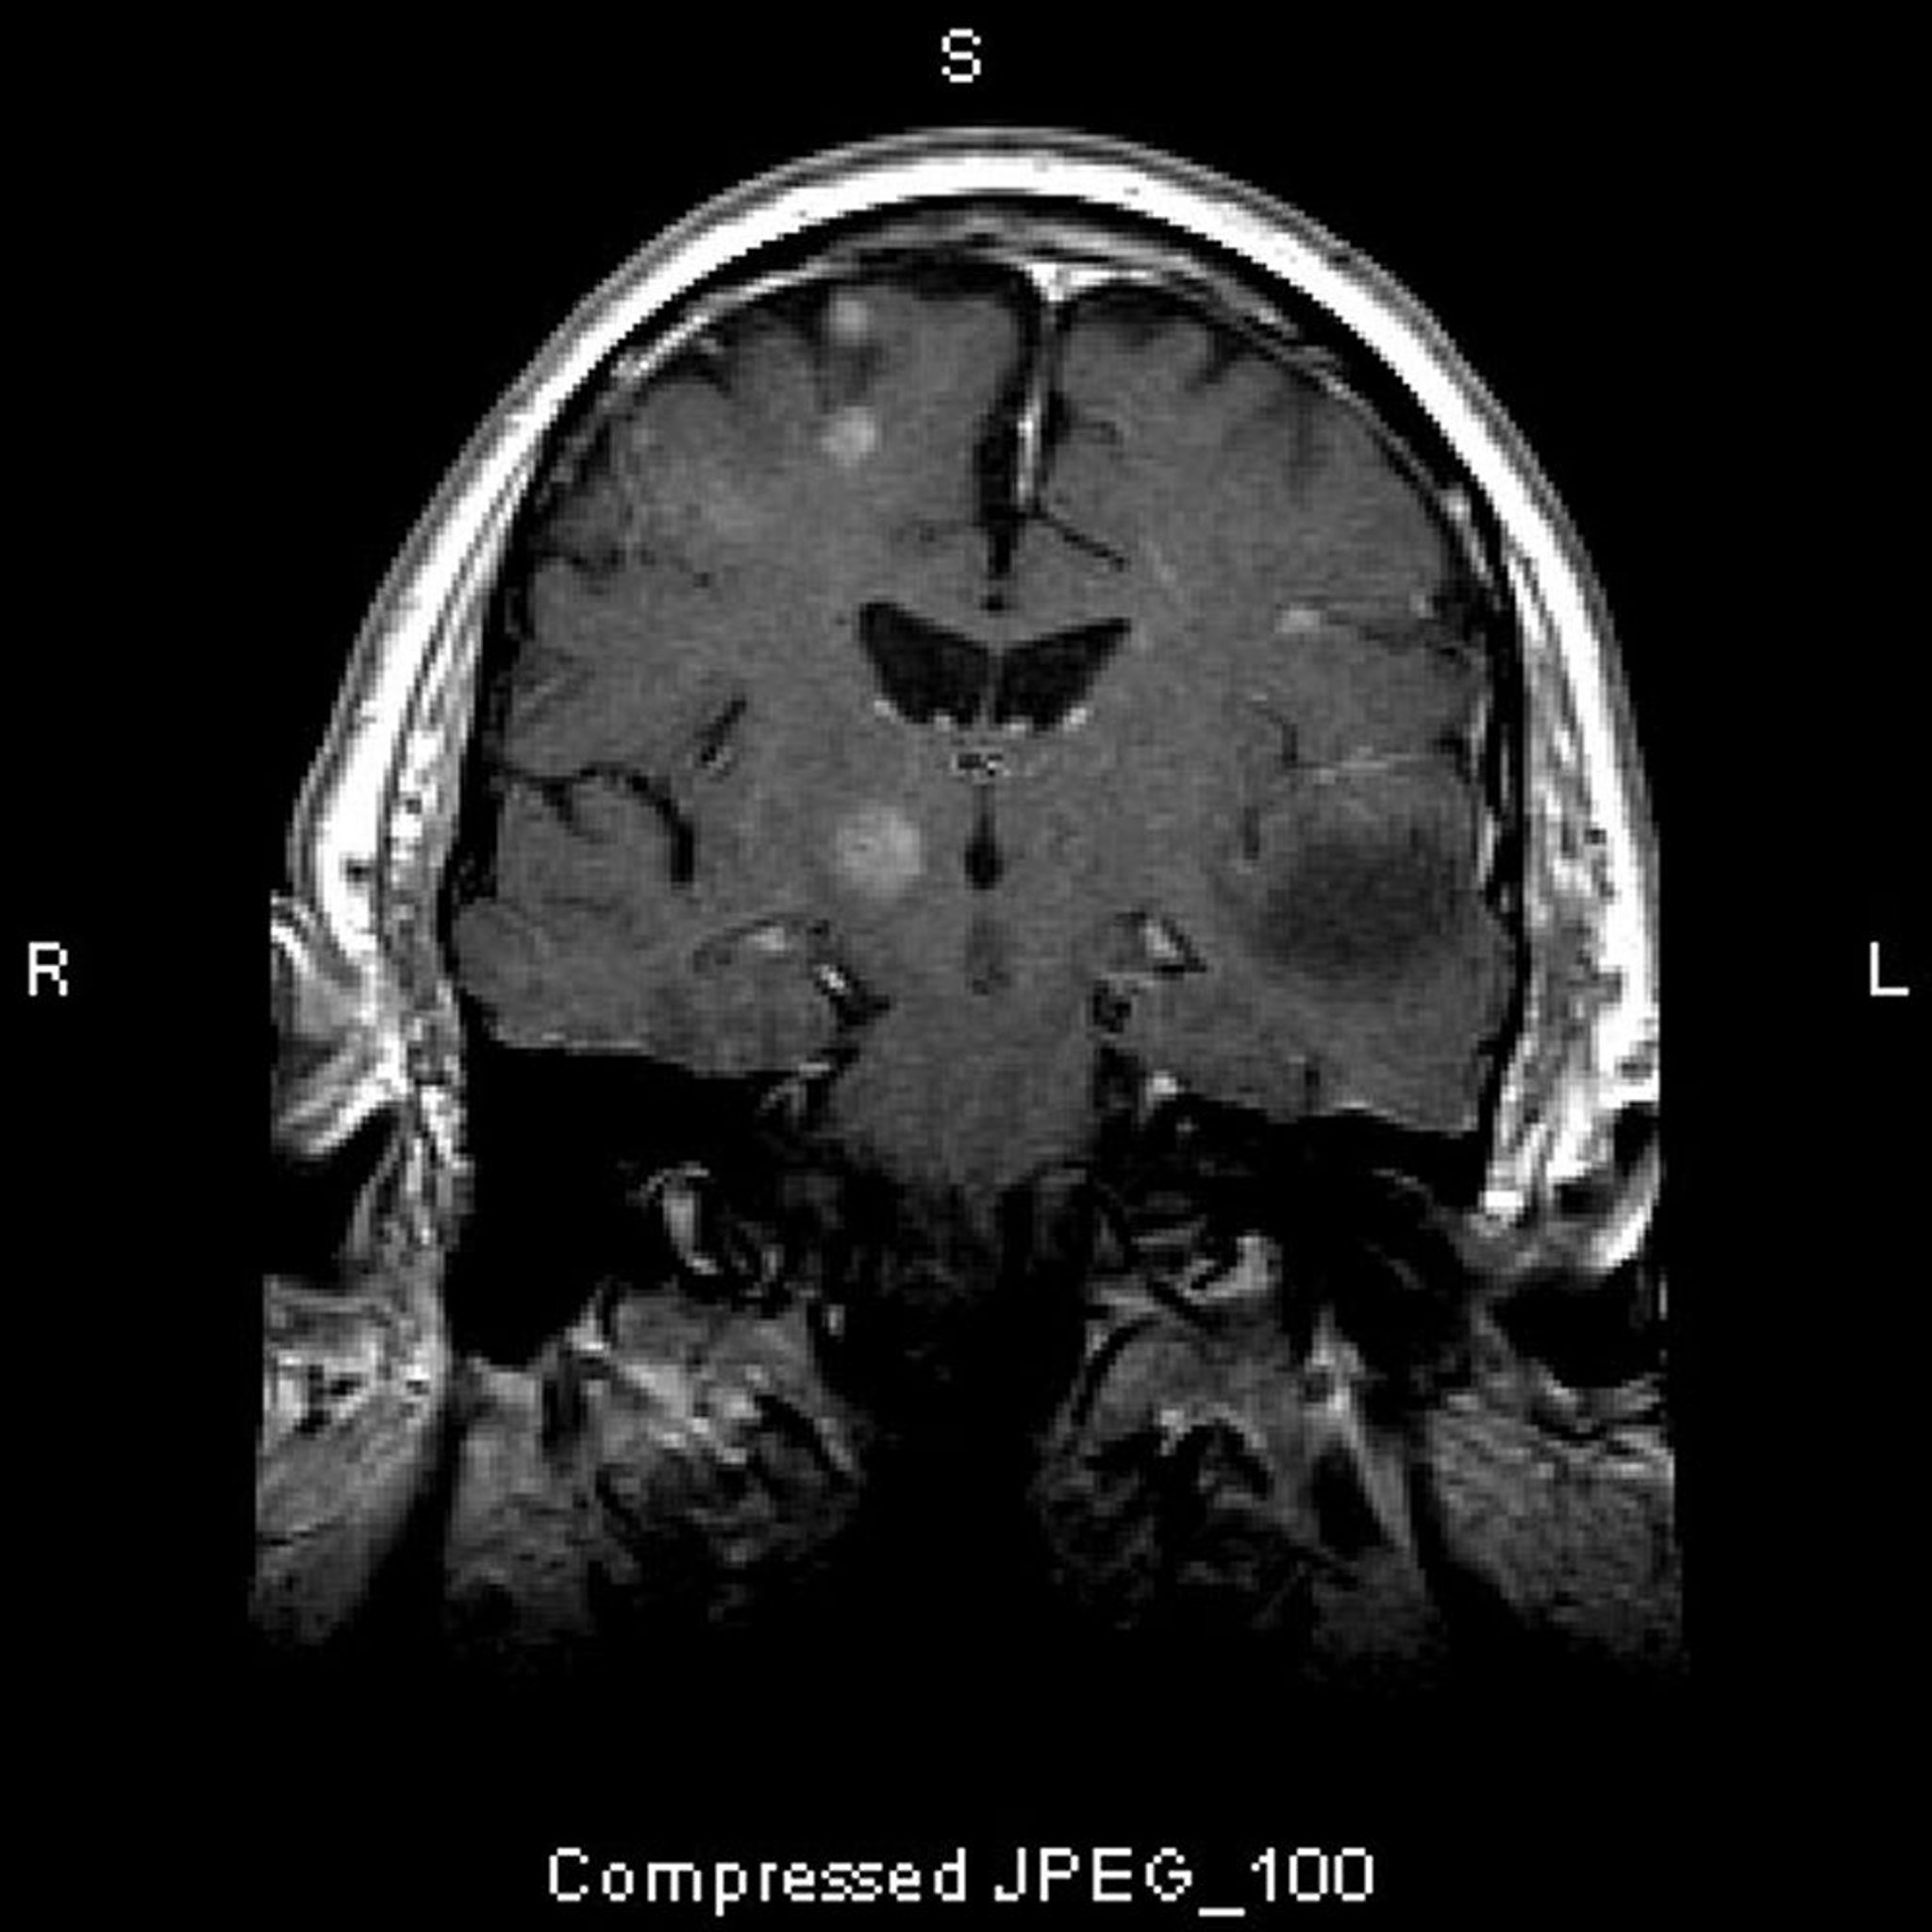

Metástasis cerebrales

Esta RM muestra múltiples lesiones cerebrales, que representan tumores metastásicos. Más del 80% de las metástasis cerebrales son múltiples.

Image courtesy of William R. Shapiro, MD.